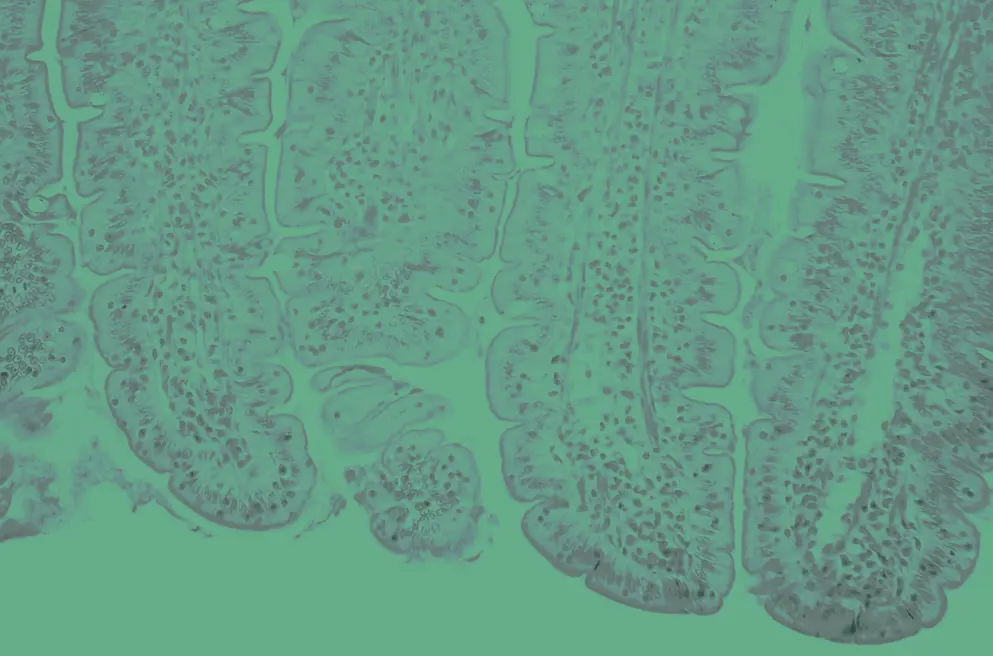

Inflammatory bowel disease

Disease information, latest news, and guidelines

Ulcerative colitis

Latest news, insights, and guideline updates